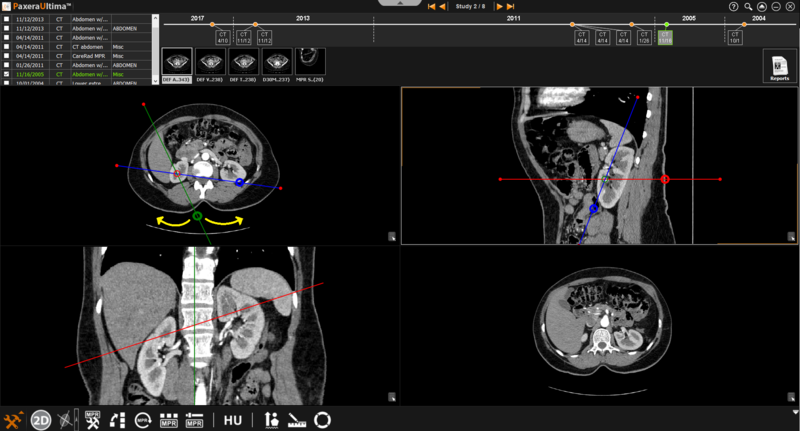

The bioblique MPR mode provides three planes (transverse, sagittal, and coronal) with lines that can rotate the angle of the planes. The image on the bottom right corner can be omitted within the bioblique mode.

» Adjust line position- The positions of the lines can be adjusted by clicking on the line of interest and dragging it in the direction of interest.

» Adjust line angle- The angle of the lines can be adjusted by clicking on the circle intercepting the line of interest and dragging it in the direction of interest.